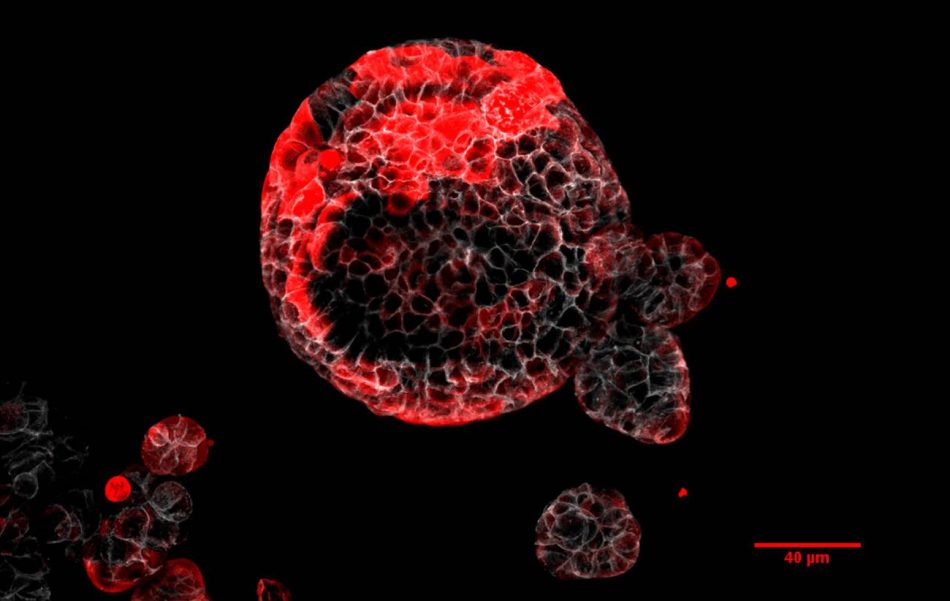

“Nuestro modelo, muy similar al progreso de la enfermedad en pacientes, nos ha permitido caracterizar el tumor primario y la dinámica de la enfermedad residual. Hemos estudiado desde micrometástasis de 3 o 4 células, a metástasis de tamaño medio, o incluso más grandes, caracterizando cómo evoluciona cada una de ellas durante la progresión de la enfermedad”, comenta Adrià Cañellas-Socias, investigador del mismo laboratorio y primer autor del estudio.

Desde hace años, los científicos saben que el cáncer de colon está compuesto por distintos tipos de células tumorales, que ejercen funciones diferentes durante la progresión de la enfermedad. Dentro de la amalgama de tipos celulares que forma los cánceres de colon, los autores han identificado una población, a la que han llamado HRC por sus siglas en inglés (High Relapse Cells o células de alta probabilidad de recaída).

Estas células presentan poca actividad proliferativa y no contribuyen al crecimiento del tumor primario. Sin embargo, grupos de HRC son capaces de desprenderse del cáncer en el colon, migrar hasta alcanzar el torrente sanguíneo, llegar al hígado y permanecer ocultas durante un tiempo tras la cirugía. En muestras procedentes de pacientes con cáncer de colon los investigadores han podido constatar la presencia de estas mismas células en los pacientes que tienen un mayor riesgo de recurrencia de la enfermedad después del tratamiento.